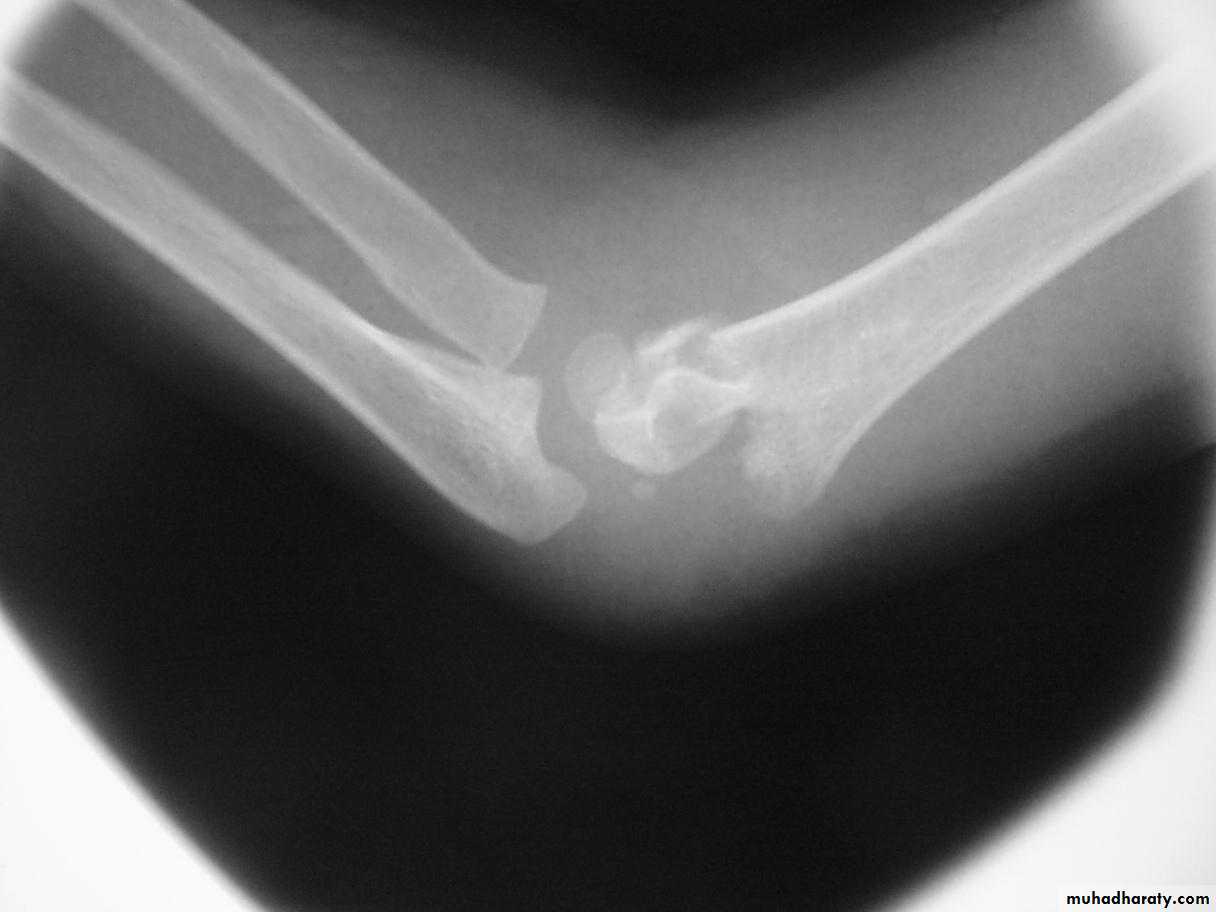

What type of supracondylar fracture

does this patient have?Flex

ionHow do the flexion patterns present?